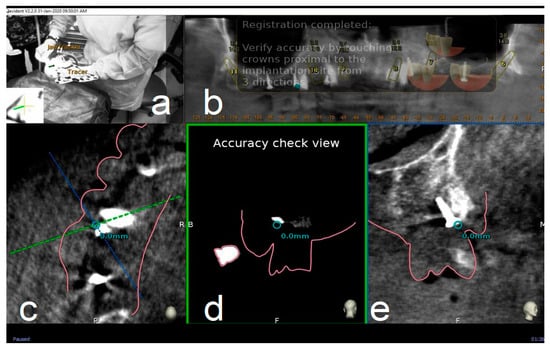

After all selected landmarks/teeth are traced, the software automatically performs registration. Sampled trace points get superimposed with CBCT 3D rendering. The complete trace and registration process takes an average of 1–2 min. The accuracy of trace registration is then assessed by touching with tracer’s ball tip any patient’s anatomical marker and confirming congruency between the touched marker and what is shown on the laptop screen (Figure 4). If the accuracy check is not satisfactory, the tracing process can be immediately repeated.

Figure 4.

The surgeon (a) can then verify the registration accuracy (b) by touching with the tracer’s ball tip one of the patient’s landmark (mini screw used in this case) (c). The matching quality can be verified from each view (d,e).